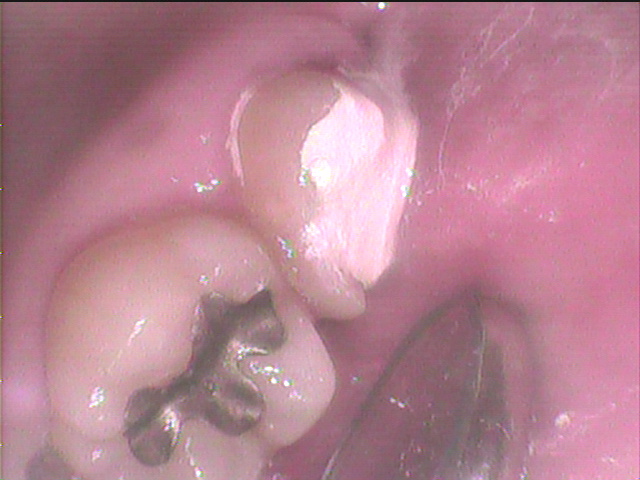

インレーが浮き上がっています。

インレーを除去するとインレーの下はレジン充填があった

さらに虫歯を追いかけて、薬剤充填をして様子を見ます。